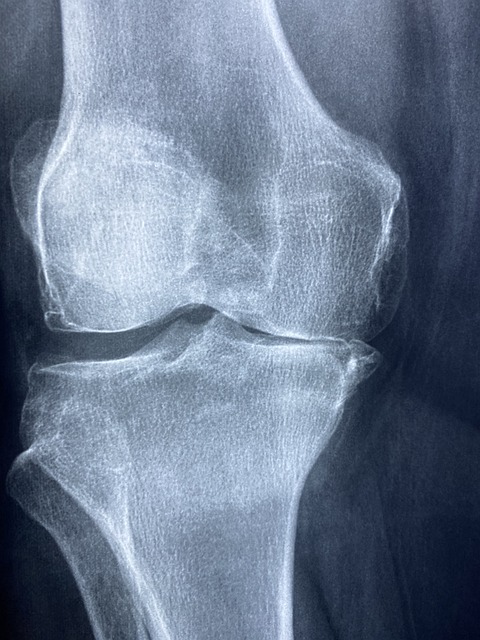

연골은 관절을 보호하는 부드러운 조직으로, 관절의 원활한 움직임을 돕고 충격을 흡수합니다. 연령 증가, 부상, 또는 특정 건강 상태로 인해 연골이 손상되거나 마모될 수 있으며, 콘드로이친은 이러한 연골의 손상을 늦추거나 관절 건강을 개선하는 데 도움을 줄 수 있습니다.

- 관절 건강 증진: 콘드로이친은 연골의 수분 보유 능력과 탄력을 유지하는 데 중요한 역할을 하여, 관절의 윤활을 개선하고 부드러운 움직임을 촉진합니다. 이는 특히 관절염이 있는 사람들에게 통증을 감소시키고 일상 활동의 품질을 향상시킬 수 있습니다.

- 연골 손상 완화: 콘드로이친은 연골 세포의 새로운 성장을 촉진하고 연골 분해를 억제함으로써 연골 손상을 줄이는 데 도움을 줍니다. 이는 연골 마모를 늦추고 장기적으로 관절의 건강을 유지하는 데 기여할 수 있습니다.